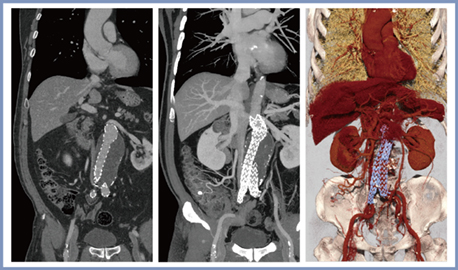

図3は,腹部大動脈ステント留置後症例であるが,腸間膜動脈に留置されたステントがSHRモードにて明瞭に描出されている。

図3 腹部大動脈ステント留置後症例のSHRモードの画像